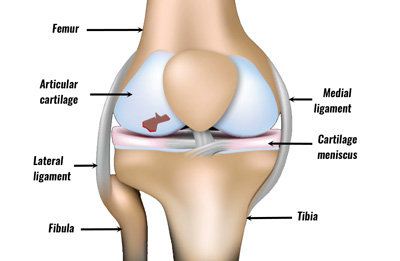

Cartilage is smooth but tough flexible connective tissue that helps bone to glide easily for movement. It is a rubber like padding that protects the end of bones that make joints & act as a shock absorber between these joints.

What is Articular Cartilage Damage?

Cartilage has a poor blood supply unlike other tissues suck as skin. Any injury to cartilage causes the underlying bones to rub against one another leading to sever pain & immobility of the joint. Cartilage Damage generally occurs at the Knee Joint, although the shoulder, ankle and other joints can also be affected from Cartilage Damage.